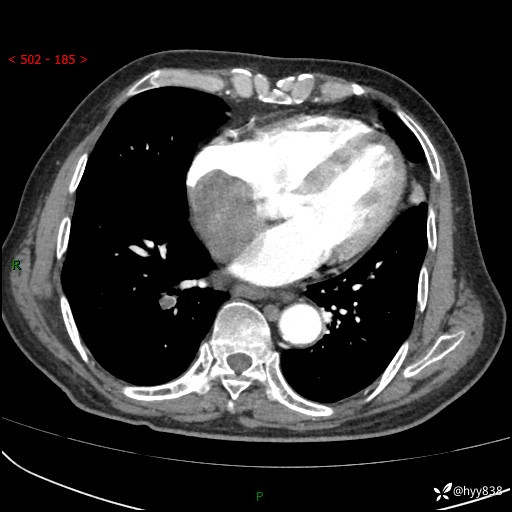

主诉:检查发现心脏肿物1周余。

现病史:患者一周余前因腹胀就诊我院消化科门诊,查心脏彩超提示右房内异常回声(粘液瘤?),无明显心慌、气喘、胸闷,无明显胸痛、咳嗽咳痰等不适,活动量增加后出现心慌、气喘不适。现为求进一步治疗,就诊我科,门诊遂以“心脏肿物”收入院。 自发病以来,精神睡眠一般,食欲尚可,大小便正常,体力下降,体重无明显变化。

胸部CT平扫+增强